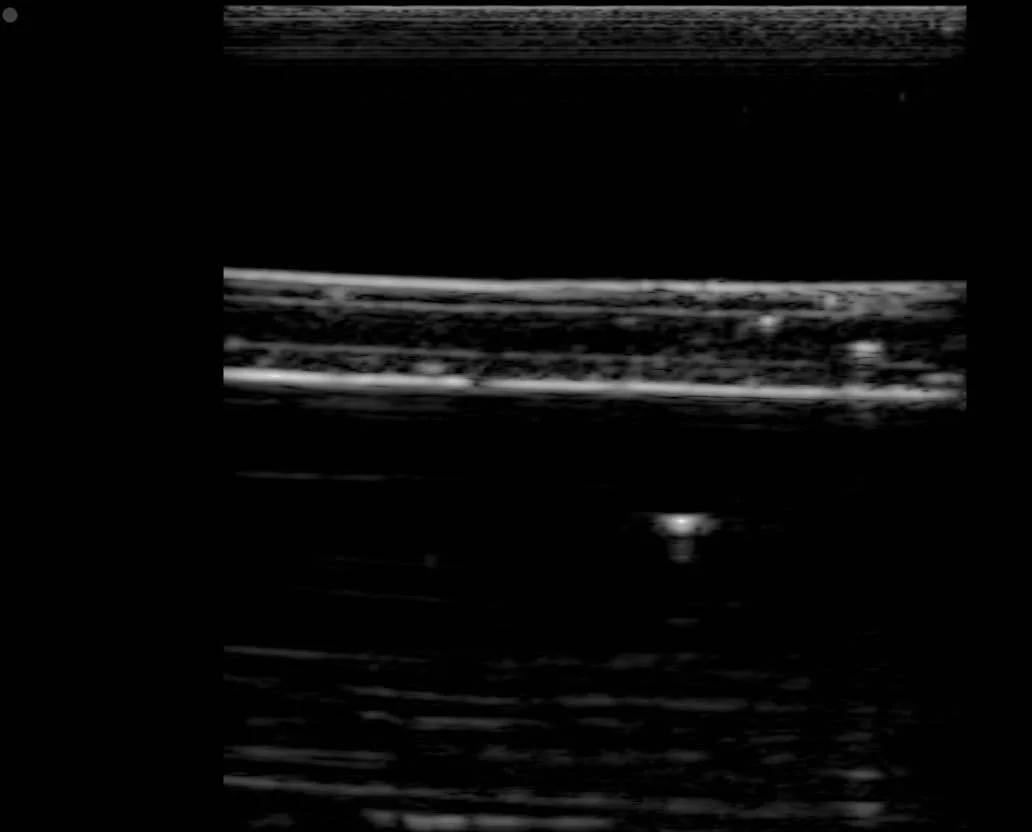

Ultrasound Images of Mechanical Simulator - Uncompressed and Uncompressed

Images from Senior Thesis

Fig 4.12 in Thesis - Uncompressed artery simulator

Fig 4.13 in Thesis - Compressed artery simulator

Fig 4.14 in Thesis - Uncompressed artery simulator, lengthwise